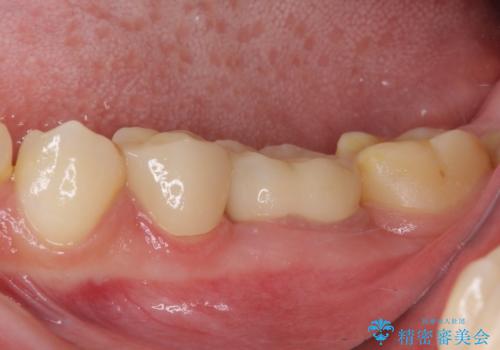

根歯の挺出(歯を引っ張り出す部分矯正)、歯周外科処置などを行った後、オールセラミッククラウンにて補綴することとしました。

当初は歯肉が腫れ上がり、大変不快な思いをされていましたが、セラミッククラウン装着後は清掃性が著しく改善し、患者様には大変満足していただきました。